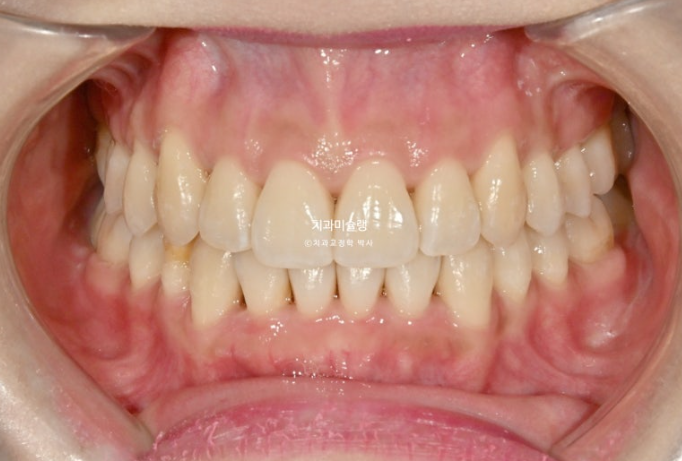

23.08~25.10

중심선의 개선, 과개교합의 개선, 덧니의 개선, 블랙트라이앵글의 개선이 보입니다.

앞니는 뒤로 들어가지도, 나오지도 않고 잘 유지되었습니다.